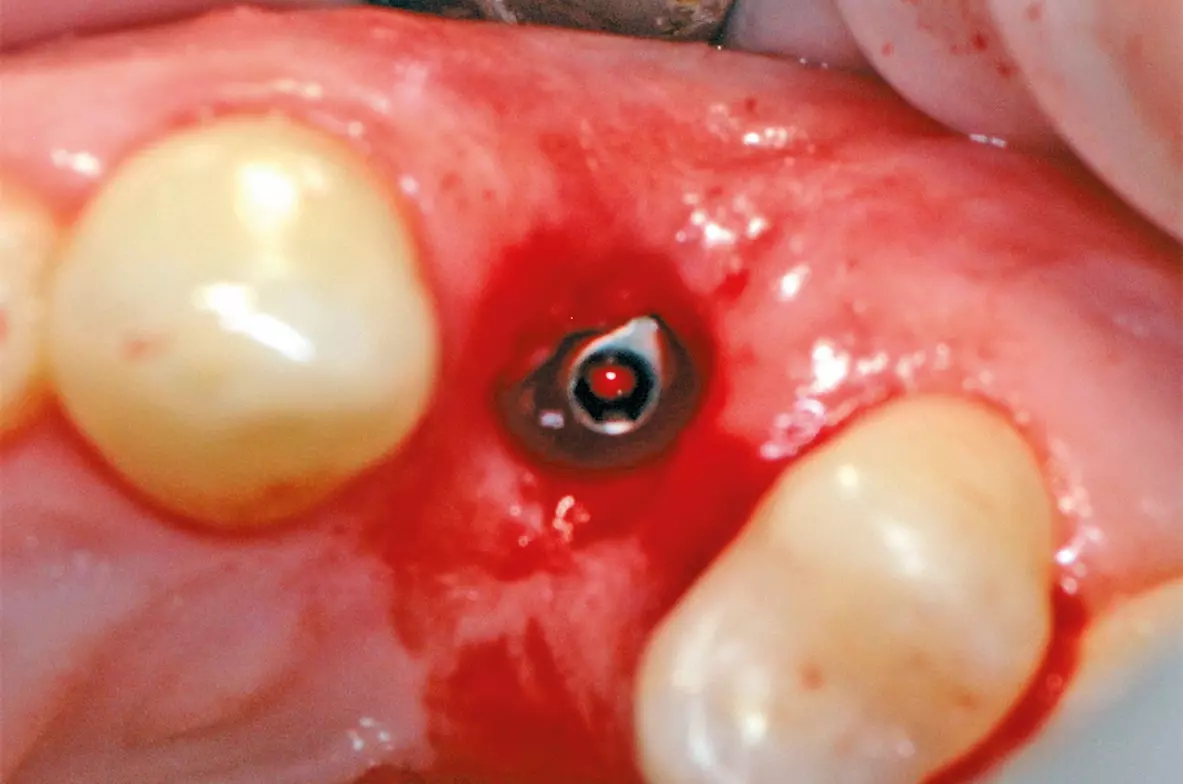

Ein Implantat konnte erfolgreich in regio 24 mit einer ausreichenden Primärstabilität inseriert werden (Abb. 20). Nach drei Monaten wurde das Implantat freigelegt (Abb. 21) und anschließend mit einer Krone versorgt (Abb. 22).